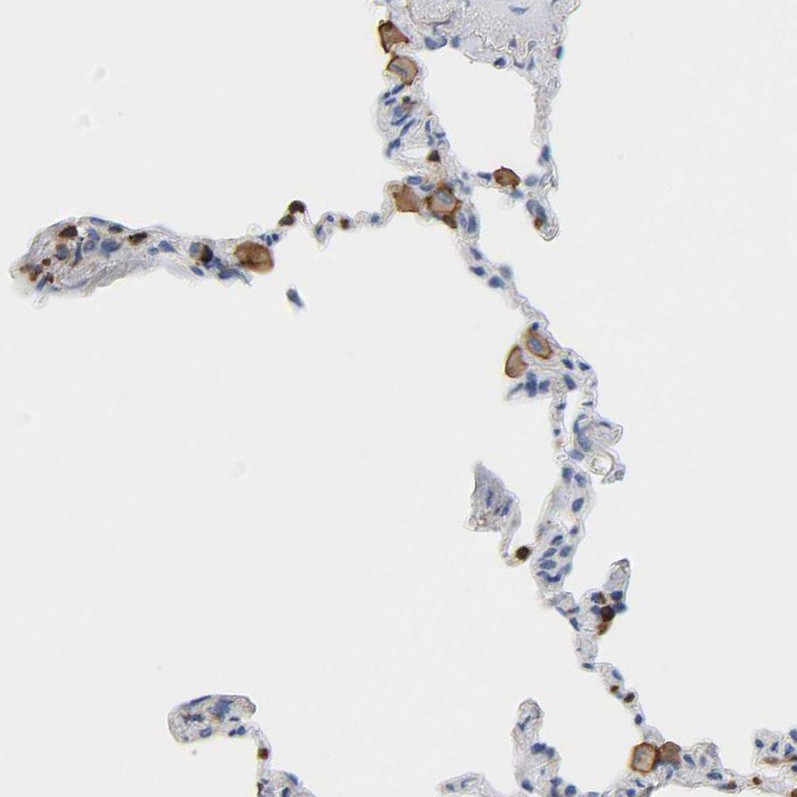

Immunohistochemistry analysis in human lymph node and skeletal muscle tissues using HPA018849 antibody. Corresponding EVL RNA-seq data are presented for the same tissues.